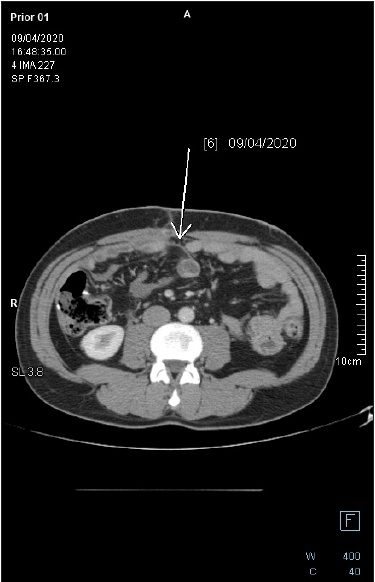

Figure 8: Follow-up axial-CECT of the midabdomen reveals complete regression of the pericolonic mucinous lesion. There is no fat stranding in the adjacent fat tissue.